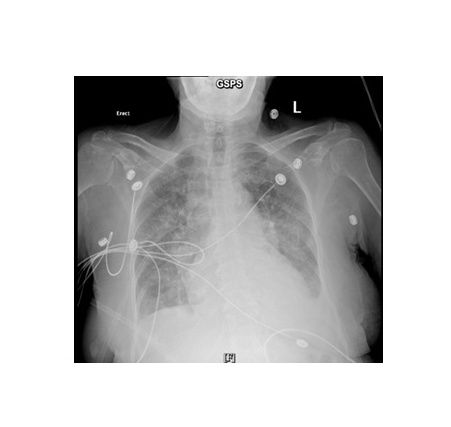

Diuretic resistance is a major therapeutic challenge in acute decompensated heart failure (ADHF). Acetazolamide, a carbonic anhydrase inhibitor, has emerged as a potential adjunct to conventional loop diuretics, as demonstrated in the ADVOR trial. We present a 74-year-old woman with acute coronary syndrome complicated by cardiogenic shock and refractory pulmonary edema despite inotropic support and guideline-directed therapy. The patient received intravenous acetazolamide 500 mg daily for three days, resulting in marked diuresis and radiographic resolution of pulmonary edema within 72 hours. The patient improved clinically. This case supports the potential utility of acetazolamide as an adjunctive strategy for overcoming diuretic resistance in ADHF.